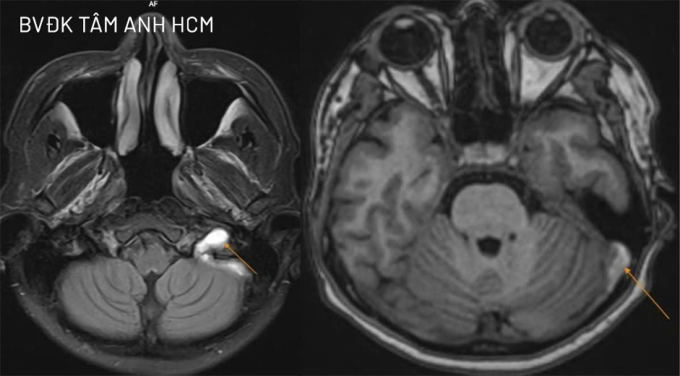

BS.CKI Cao Hoàng Trọng, Khoa Thần kinh, Trung tâm Khoa học Thần kinh, Bệnh viện Đa khoa Tâm Anh TP HCM, cho biết chị Mai tỉnh táo, không nói đớ, không yếu liệt tay chân, không co giật. Kết quả chụp MRI 3 Tesla khảo sát mạch máu não người bệnh cho thấy cục máu khối hình thành ở tĩnh mạch cảnh trong bên trái, làm tắc nghẽn dòng máu tại đoạn hành. Huyết khối đang ở giai đoạn bán cấp và đã lan lên xoang sigma, một phần xoang ngang bên trái.